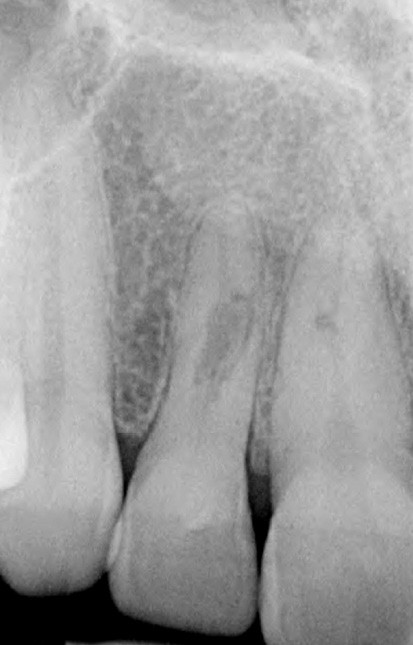

Si l’étude de Peters [18] nous montre que l’instrumentation laisse 35 % du volume canalaire non instrumenté, Ricucci et Siqueira montrent que la préparation physico-chimique n’élimine que partiellement les tissus nécrotiques à l’entrée des canaux latéraux, des isthmes et des ramifications apicales, en laissant des tissus enflammés et infectés, en association avec des lésions apicales [29] (fig. 4 et 5).

Fig. 4 – Coupe d’une racine mésiale de molaire mandibulaire avec deux canaux traités. Coupe à 3 mm de l’apex, coloration Brown et Brenn, technique modifiée par Taylor. Ces images montrent un isthme étroit avec une infection bactérienne, ce qui prouve l’importance de désinfecter et d’inclure l’isthme dans les traitements conventionnels et dans les rétropréparations apicales en chirurgie endodontique.